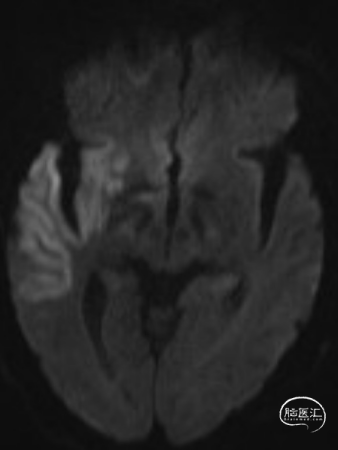

查头颅MRI:右侧基底节区、右侧顶颞岛叶急性脑梗死。